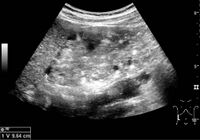

Figure 7. Advanced polycystic kidney disease with multiple cysts.[1]

Complex cysts can have membranes dividing the fluid-filled center with internal echoes, calcifications or irregular thickened walls. The complex cyst can be further evaluated with Doppler US, and for Bosniak classification and follow-up of complex cysts, either contrast-enhanced ultrasound (CEUS) or contrast CT is used (Figure 6). The Bosniak classification is divided into four groups going from I, corresponding to a simple cyst, to IV, corresponding to a cyst with solid parts and an 85–100% risk of malignancy.[1] In polycystic kidney disease, multiple cysts of varying size in close contact with each other are seen filling virtually the entire renal region. In advanced stages of this disease, the kidneys are enlarged with a lack of corticomedullary differentiation (Figure 7).[1]